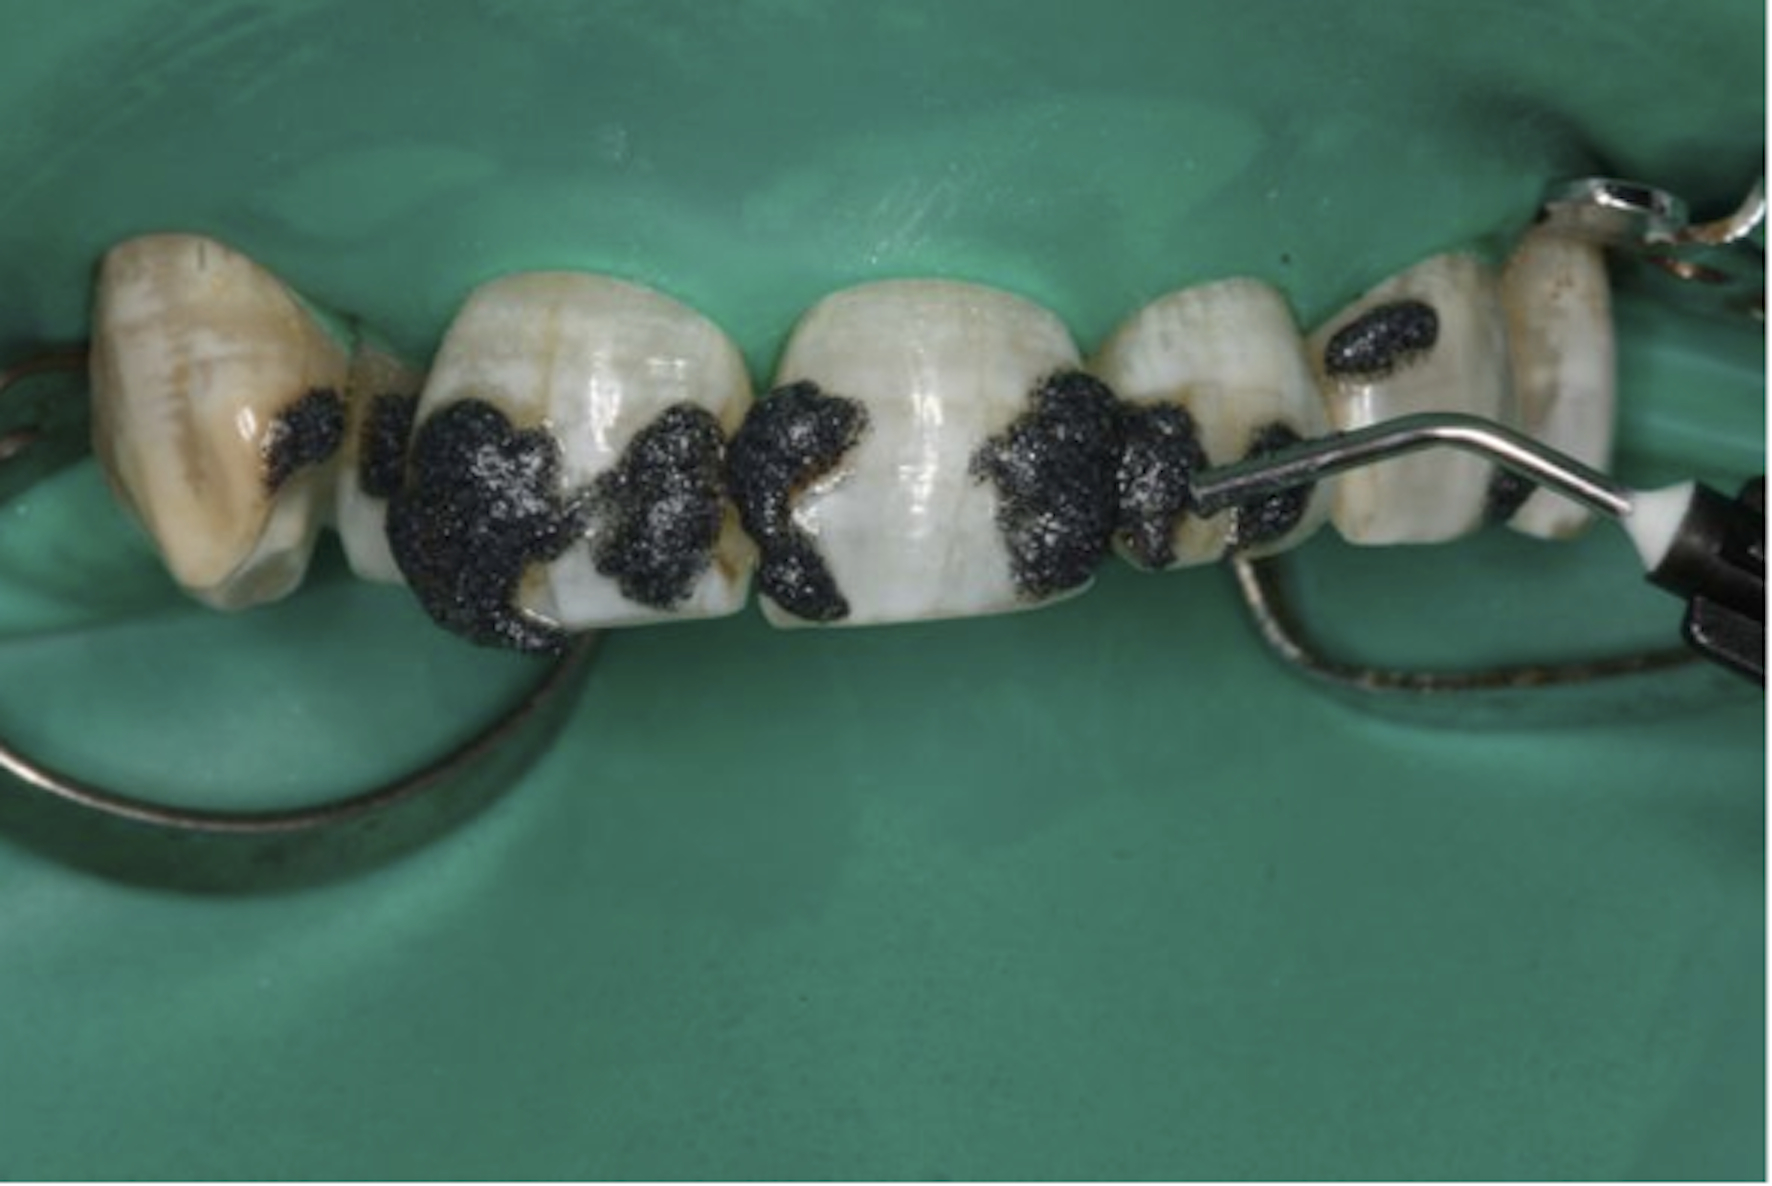

The generalized presence of stain, particularly on anterior teeth, provides an unaesthetic appearance with a negative impact on the patient. The aim of this paper is to report a case of severe chromatic alterations treated with enamel microabrasion associated with infiltration of low-viscosity resin. The intense brownish pigmentation and white spots of fluorosis lose their whitish appearance and look similar to sound enamel. This association of techniques, which might be an alternative to white-masking of intense pigmentation, showed optimal aesthetic results.